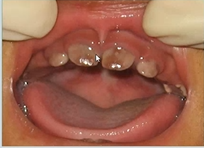

what is this an example of?

abnormally shaped teeth

what causes teeth abnormalities and how can it be presented?

congenital Syphilis → vertically transmitted from the mother

Hutchinson’s incisors

Mulberry molars